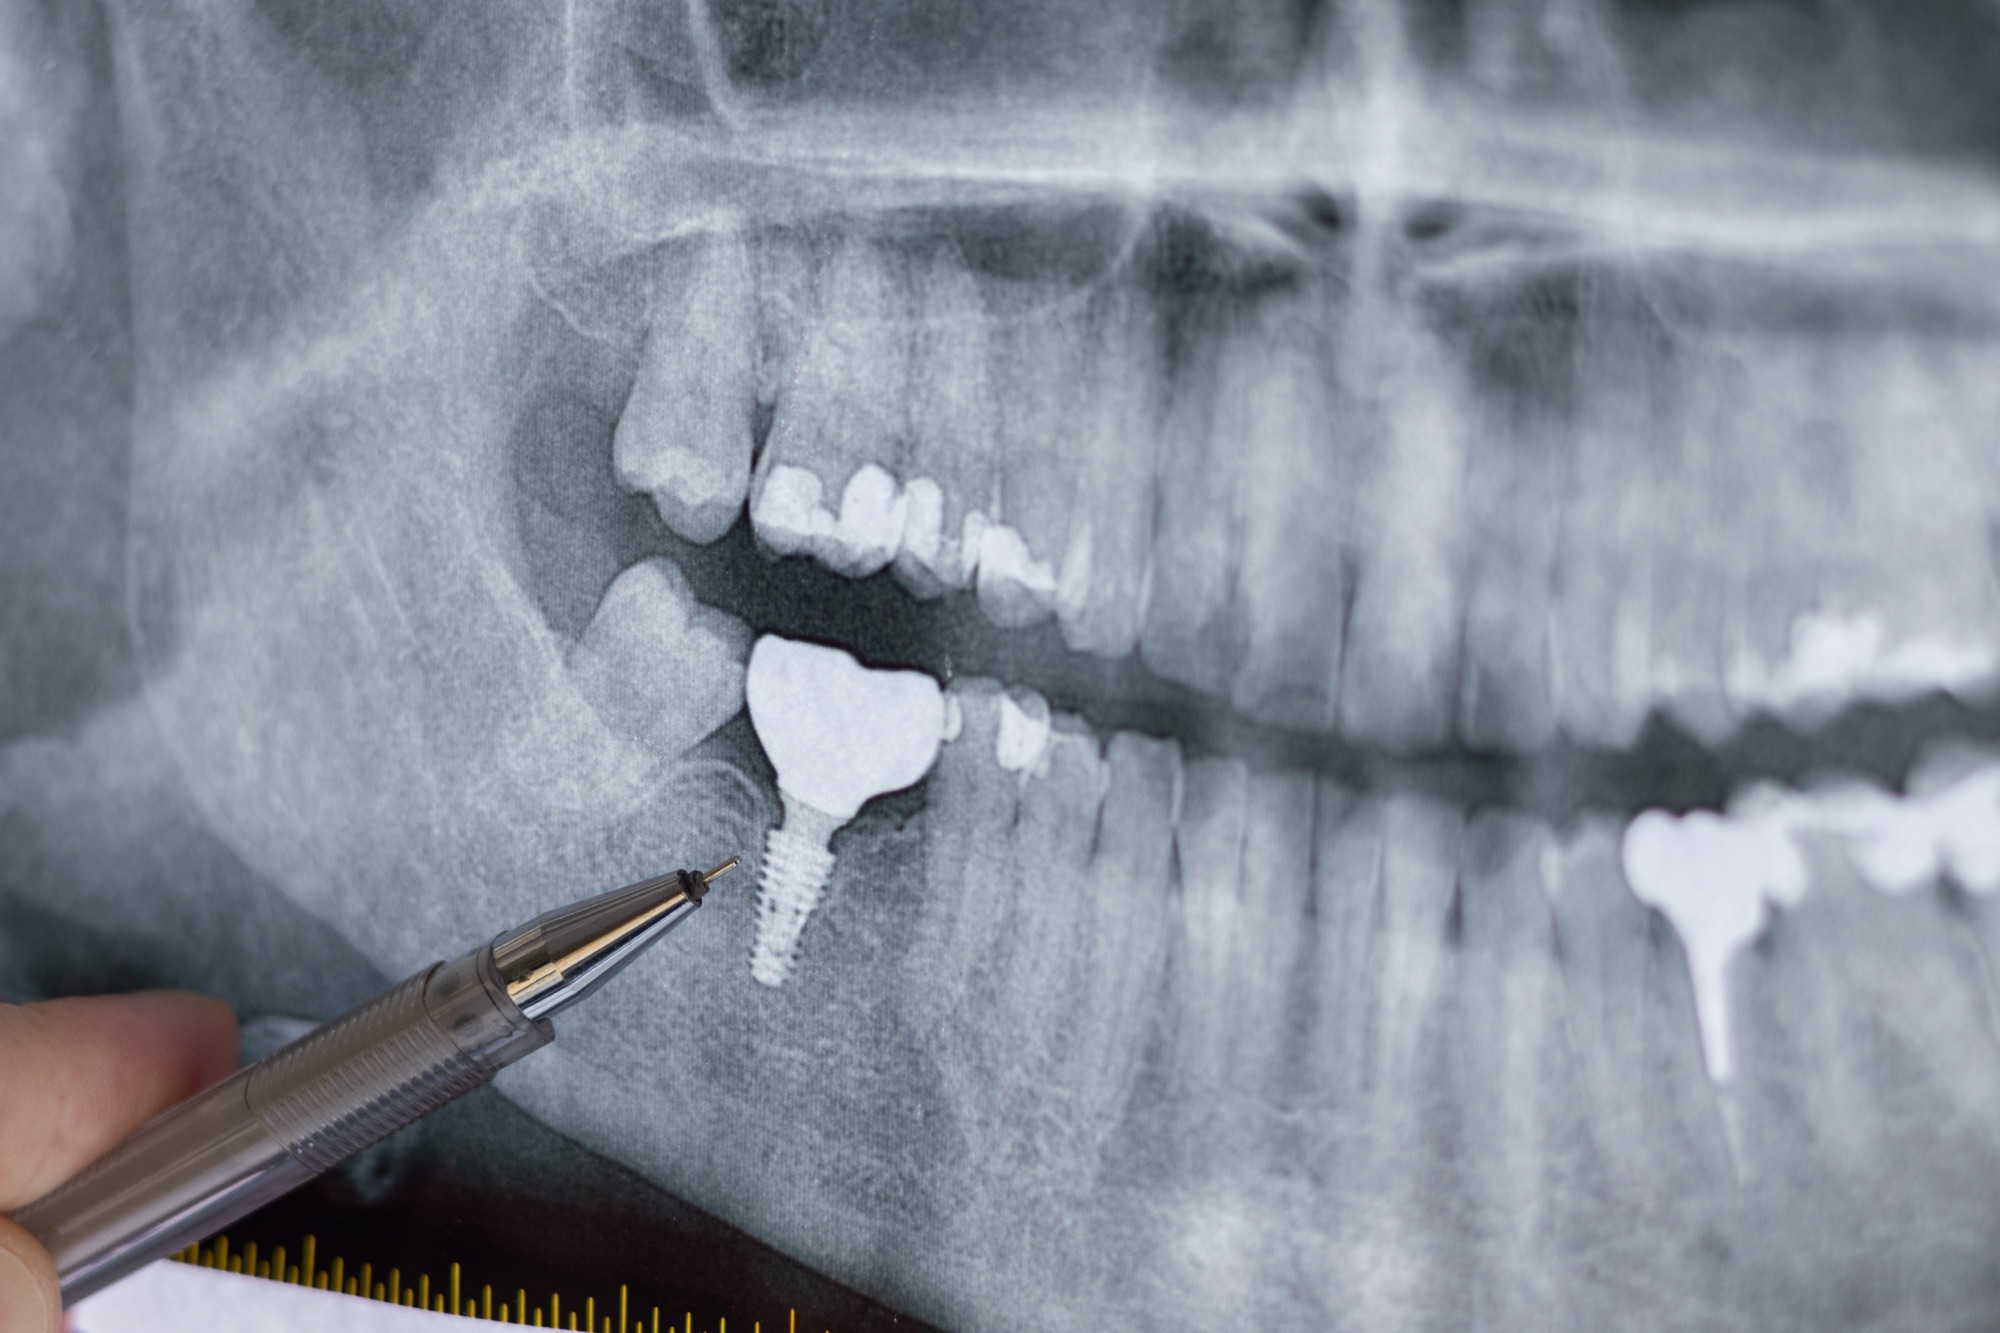

インプラント治療を検討する際、多くの方が一番に抱く不安は「手術はどれくらい痛いのか?」ということです。「顎の骨にネジを打つ」というイメージから、強い恐怖心を感じて一歩踏み出せない方も少なくありません。

結論からお伝えすると、インプラント手術中の痛みは、適切な麻酔管理によってほとんど感じることがありません。この記事では、歯科医師の視点から手術中・術後の痛みの実態と、歯科恐怖症の方でも安心して受けられる最新の対処法を詳しく解説します。

・CT・ガイド手術:事前に3Dシミュレーションを行うことで、最短時間で正確に手術を終えることができ、身体への負担を減らせます。